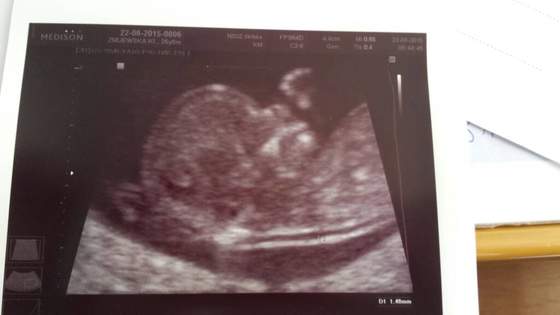

ImageUploadedByForum BabyBoom1434993087.513071.jpg

• ImageUploadedByForum BabyBoom1434993087.513071.jpg

21,7 KB · Wyświetleń: 92